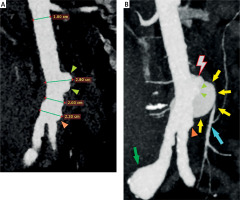

Figure 3

Computed tomography angiography (CTA), MPR reconstruction, coronal view (A – light green arrowheads: focal aortic dilatation near the rupture site, orange arrowheads: focal aortic dilatation above the aortic bifurcation), (B – red lightning bolt: aortic rupture, red lightning bolt: aortic rupture, light green arrowheads: focal aortic dilatation near the rupture site, orange arrowheads: focal aortic dilatation above the aortic bifurcation, light blue arrow: inferior mesenteric artery, green arow: right common iliac artery aneurysm)